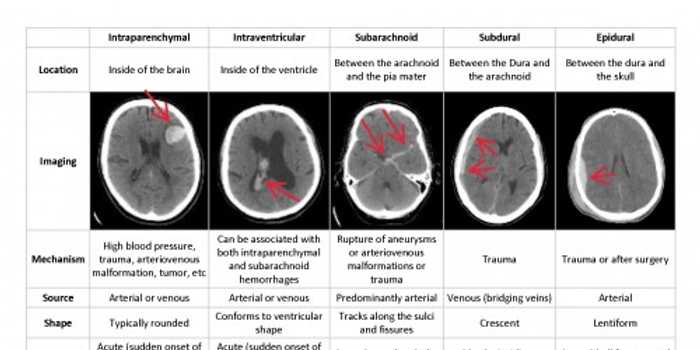

如果说手术室里的出血是“正在进行时”,需要即时反应,那么急诊室里还有一种出血,是“生死时速”,必须分秒必争——那就是脑出血。脑出血是中风里最致命的一种,死亡率能超过30%-3。送到急诊的病人,头痛欲裂,意识模糊,医生第一件要紧事就是做头部CT,看看脑子里是不是在出血。可是,深更半夜,放射科医生不一定随时在岗;就算在,一张一张片子仔细看,时间就这么滴滴答答地流走了。

这时候,ai出血在急诊影像诊断上的威力就显出来了。有的医院引进的AI系统,能够在30秒内完成对CT片的初筛,圈出出血的位置,准确度高达95%-5。更有研究数据显示,使用AI辅助分析CT,能让脑出血的死亡率下降超过三成-3。这个数字背后,是一个个原本可能破碎的家庭。对急诊科医生来说,这个AI就像一个永远在岗、瞬间响应的超级助理,它把“从拍片到出报告”这个漫长等待过程,压缩成了“立等可取”。医生不是被取代了,而是被增强了,他能更快地做出手术还是保守治疗的关键决策,信心也更足了-5。